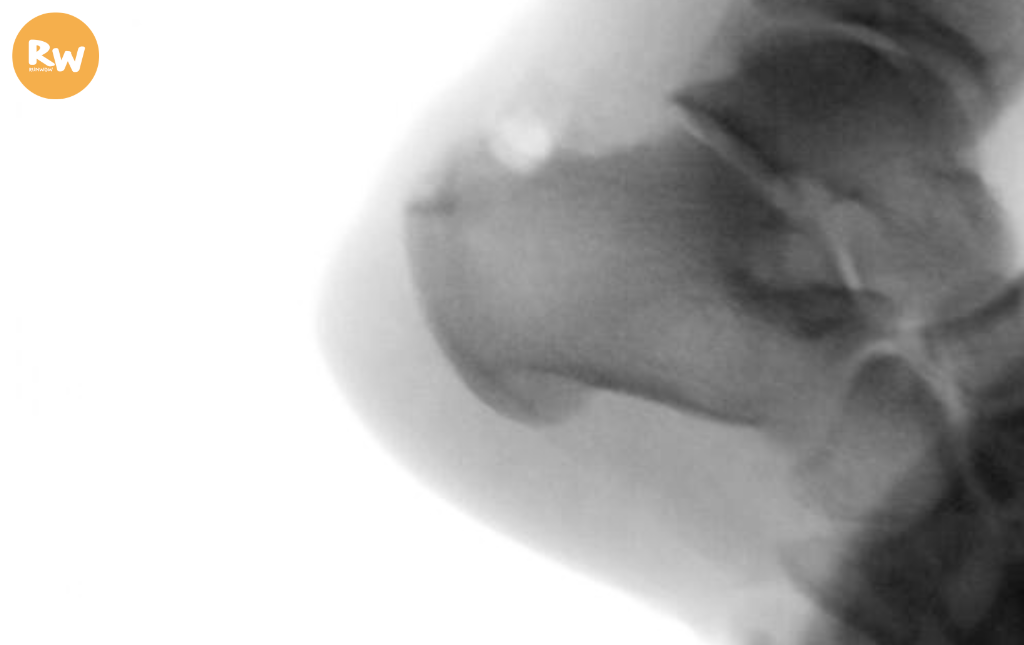

可是跑步兩年後,Samson喜悅戛然而止,右腳開始疼痛,後來連行走皆感艱難。X光檢查顯示,阿基里斯腱鈣化嚴重,並伴隨骨刺突出。他四處求醫,疼痛至考慮手術,終聯繫舊同學兼骨科專科醫生Bill哥。Bill哥仔細診斷,指出多重問題:阿基里斯腱退化、骨刺突出壓迫神經、滑囊炎併發。「即使進行骨刺手術,筋腱本身仍不健康。」Bill哥直言:「在你這個年齡,最多日後不再跑步即可。」

Bill哥的治療哲學,體現骨科專科醫生的務實與細膩。阿基里斯腱問題在長跑者中極常見,Samson屬嚴重類別,筋腱骨交界已鈣化,不手術只會加速衰退:「若繼續跑步,將加速筋腱衰退及功能喪失。」治療上,會以保守治療為首選:先進行全面評估,包括臨牆檢查、X光、超聲波、MRI,以確定病變程度。「無人喜手術,我們亦不樂於每例皆手術。須盡試所有方法,方考慮手術。」Bill哥指出,止痛藥可暫緩症狀,提供舒緩,但始終非長遠根治之道。